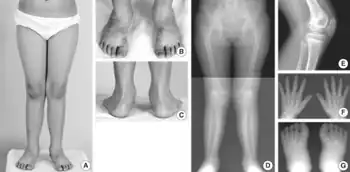

a-c) Genu valgum, forefoot adduction d) Genu valgum e) double layered patella f) shortening metacarpals/phalanges g) triangular medial cuneiforms

Autosomal recessive multiple epiphyseal dysplasia (ARMED), also called epiphyseal dysplasia, multiple, 4 (EDM4), multiple epiphyseal dysplasia with clubfoot or with bilayered patellae,[1] is an autosomal recessive[2] congenital disorder affecting cartilage and bone development. The disorder has relatively mild signs and symptoms, including joint pain, scoliosis, and malformations of the hands, feet, and knees.[3]

Some affected individuals are born with an inward- and downward-turning foot (a clubfoot). An abnormality of the kneecap called a double-layered patella is also relatively common. Although some people with recessive multiple epiphyseal dysplasia have short stature as adults, most are of normal height. The incidence is unknown as many cases are not diagnosed due to mild symptoms.